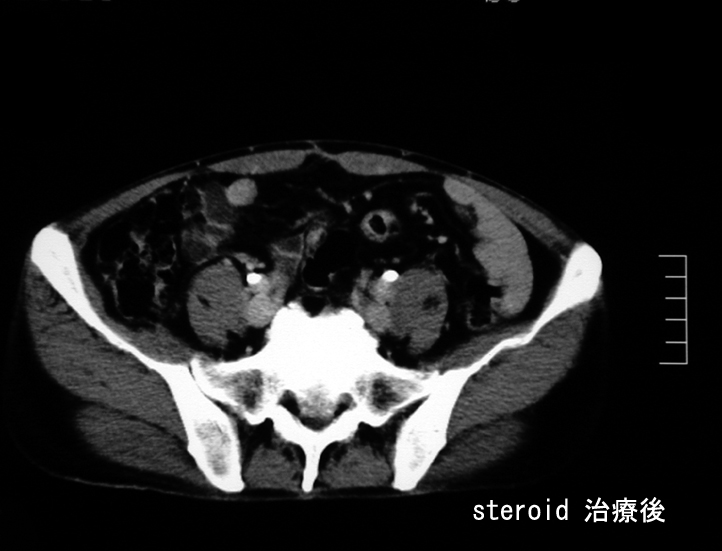

悪性リンパ腫や膵癌など悪性腫瘍は否定され自己免疫性膵炎と診断し, steroid治療を開始する。約2ヶ月の投与で, 膵、腹腔腫瘤は著明に縮小または消失しました。steroid減量中に黄疸が出現, 画像診断で硬化性胆管炎の合併をうたがいsteroidを増量、黄疸は消失。以後steroid をゆるやかに漸減し中止したが症状の再発はない。

Steroid 治療2ヶ月後のCT; 腫瘤性病変の著明な縮小と消失が確認できる。